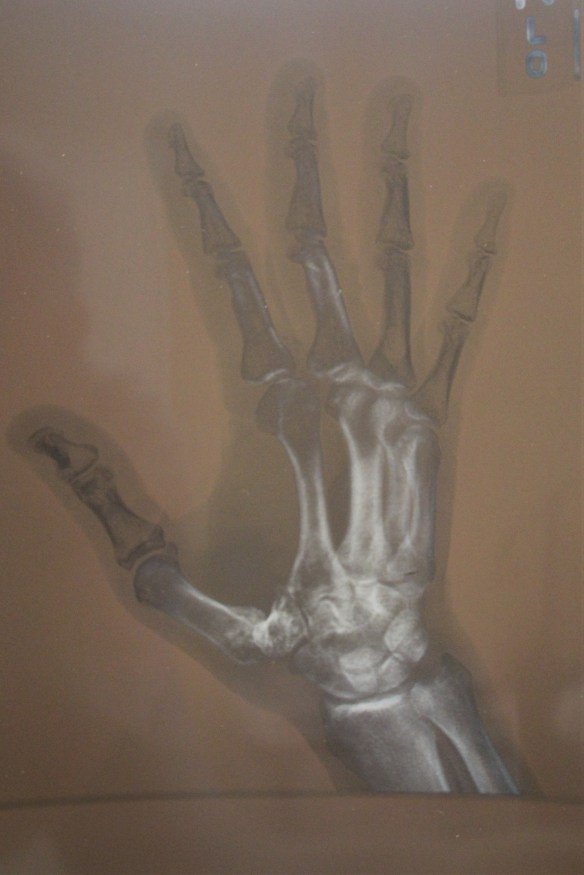

A month ago I voluntarily had surgery on my right hand; more specifically on my thumb. I had a condition where I over used my thumb by gripping things and squeezing things very hard and often over the course of many years. The pain started about ten years ago, but gradually became worse to the point where I could barely hold a pen or pencil and write legibly. Grabbing a glass became painful and squeezing the handle on a hose sprayer impossible to do. I tried on multiple occasions steroid shots and for a while they helped, but eventually didn’t. The base of my thumb which adjoins my hand bone had no cartilage (cushion) between them which created the pain plus the ligaments were badly worn out. The only alternative was surgery or not use my right hand which is my predominate hand for just about everything. I can’t really tell by this photograph of my x-ray where the exact problem lies, but the surgeon knew, thankfully!

Both images were taken before surgery. I am healing know, but the doctor says it may take up to six months to feel normal again, and up to a year to be 100%. Immediately after the surgery the pain was intense, but it diminishes as each day passes.